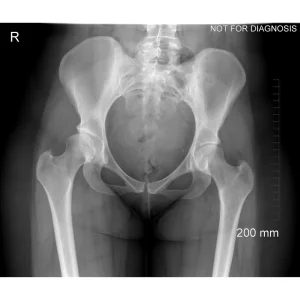

Hip dysplasia occurs when the hip socket does not fully cover the ball of the hip joint. This can be understood using imaging studies such as X-rays, CT scans, or MRI.

Diagram 2: Hip Dysplasia

• Shallow acetabulum with reduced coverage of the femoral head

• Increased stress on the edge of the joint

• Higher risk of pain, labral tears, and early arthritis

These diagrams are commonly used in clinic to help patients visualize the problem and understand how PAO corrects hip mechanics. Dr Grammatopoulos will review your X-rays alongside these illustrations to explain your individual anatomy and surgical plan.